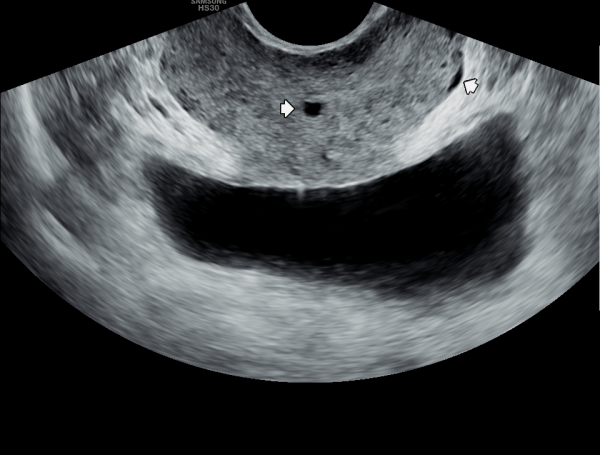

수년전 부터 하복부 통증과 사정시 혈정액을 주소로 여러 비뇨기과와 상급병원에서 치료를 했으나 증상의 호전이 없다고 내원당일 검사한 경직장 전립선 초음파 검사상 사정관 입구에 결석과 사정관의 낭종이 관찰되는 초음파 사진입니다.

The transrectal prostate ultrasound image taken on the day of the patient's first visit shows a stone at the ejaculatory duct opening and a cyst in the ejaculatory duct.

The patient had been experiencing lower abdominal pain and hematospermia during ejaculation for several years, and had received treatment at multiple urology clinics and advanced hospitals without symptom improvement.